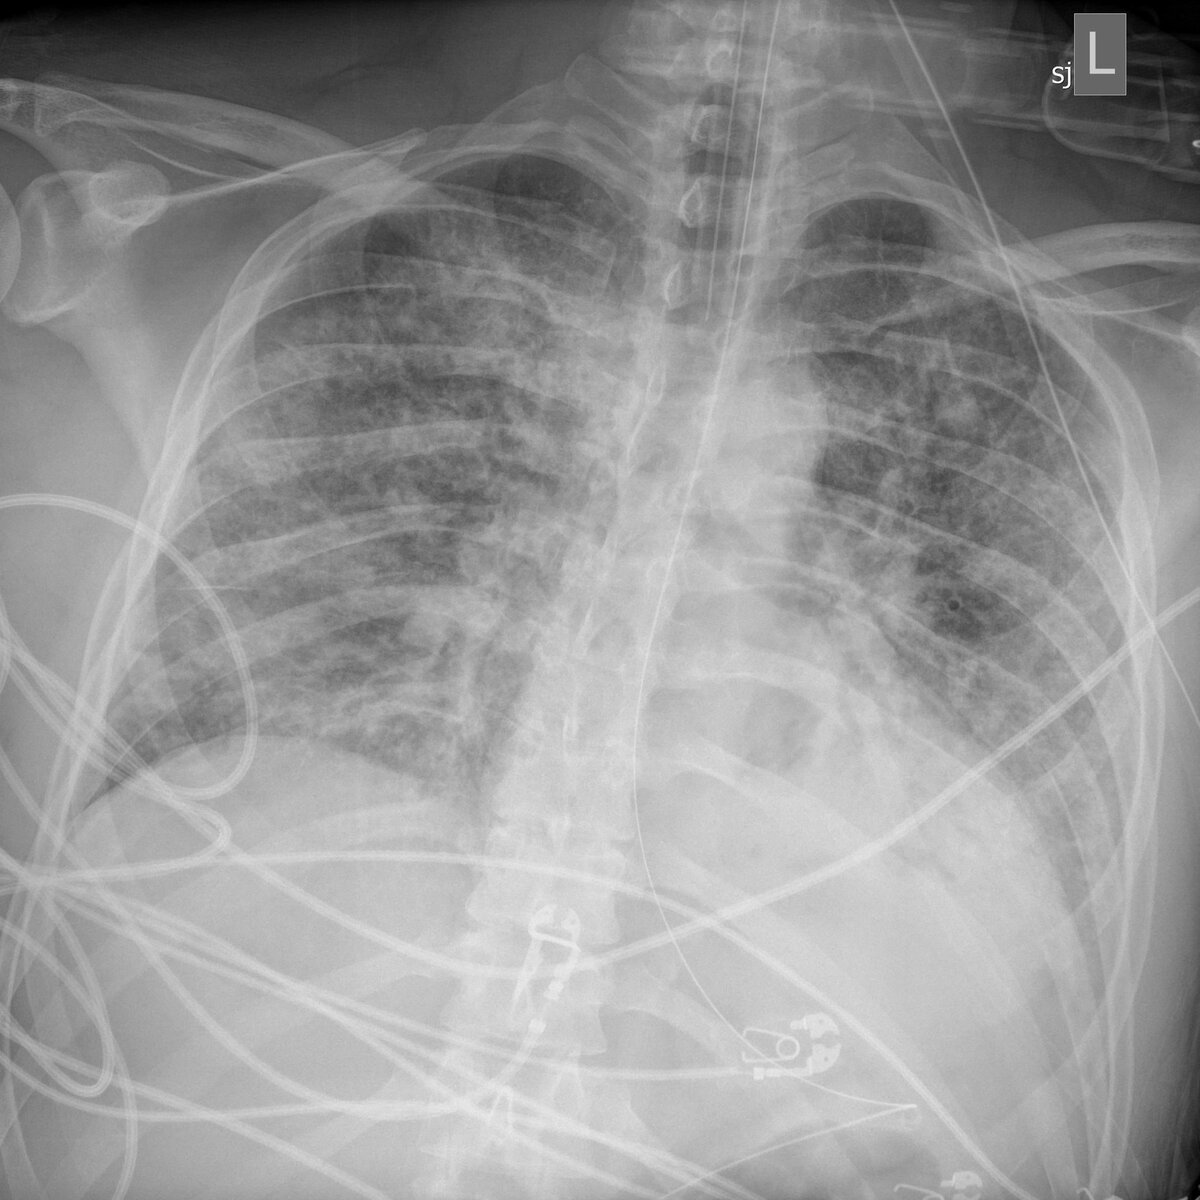

Теперь, несмотря на все усилия врачей, его легкие на последнем рентгеновском снимке были абсолютно белыми, практически без воздуха. «Один из худших рентгеновских снимков грудной клетки, который я когда-либо видел» - прокомментировал доктор Пол Керриер, еще один из его врачей.

Рентген снимок легких Джима Белло 14го марта

Вокруг трубок начала появляться кровь, пришлось остановить антикоагулянты [лекарства, которые предотвращают свертываемость крови]. Рентгенография грудной клетки не обнадеживала. 13 марта было много жидкости и воспалений, но можно было все еще разглядеть легкие. 18 марта снимок был хуже, но пространство в легких все еще было. К 20 марта его легкие были, как белое полотно.

Рентген снимок легких Джима Белло 27го марта

Через три дня на рентгене появился небольшой просвет в левом легком. Сначала ему было чуть лучше, а потом стало намного лучше.

Рентген снимок легких Джима Белло 4го апреля